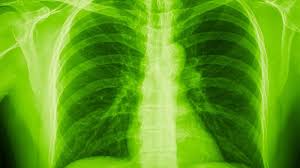

Recovered COVID-19 patients left with permanent lung damage, claims health experts

The COVID-19 pandemic has brought about an serious health scare in the lives of numerous human beings especially those who have faced the health scare. A new study has claimed that thousands of coronavirus survivors have been left with "irreversible lung damage" after contracting the illness. It is a known fact that the virus attacks the lungs first and based on certain study doctors have revealed that patients are suffering from scarring on the lungs as well as symptoms such as coughing and fatigue. After surviving the virus patients are invited back to hospital to conduct a scan on their lungs. "In the six-week scans we're seeing, so far I would say between 20 and 30 per cent of patients who have been in hospital appear to show some early signs of lung scarring”, Dr Hare said.

Studies in China have previously shown that Covid patients still had lung damage after they were discharged from hospitals.Data from other viruses such as Sars and Mers found that up to 60 per cent of patients experienced health conditions similar to pulmonary fibrosis after surviving Covid. Dr Hare said he is concerned due to the fact that so many people in the UK have had Covid and said many doctors are worried about the “sheer amount of patients we will need to treat”.

Prof Gisli Jenkins, of the National Institute for Health Research said:"My real concern is that never before in our lifetime have so many people been subject to the same lung injury at the same time."The global cumulative count of confirmed coronavirus cases is approaching nine million, with 133,326 cases recorded over the past day, the World Health Orgsation (WHO) said in its daily situation report on Tuesday.Over the past 24 hours, 3,847 people died from COVID-19 worldwide, taking the cumulative death toll to 469,587 fatalities, according to the report.